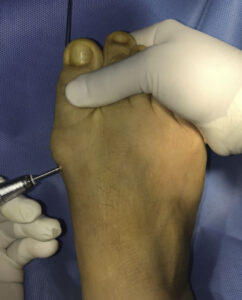

Su empleo más difundido es la cirugía percutánea del pie o cirugía láser donde podemos tratar juanetes, metatarsalgias o fascitis plantar con control de rayos X, aunque también existen técnicas en cirugía de la mano, en algunos tipos de fracturas, etc. Las incisiones suelen ser milimétricas y a través de ellas se introduce el material que permite realizar la cirugía como bisturí, fresas o agujas entre otros.

Por lo general la anestesia que se emplea durante el proceso es anestesia local o regional limitada al área que vayamos a tratar, lo cual permite un control local completo del dolor evitando anestesiar zonas donde no se interviene, lo que favorece la recuperación postoperatoria.